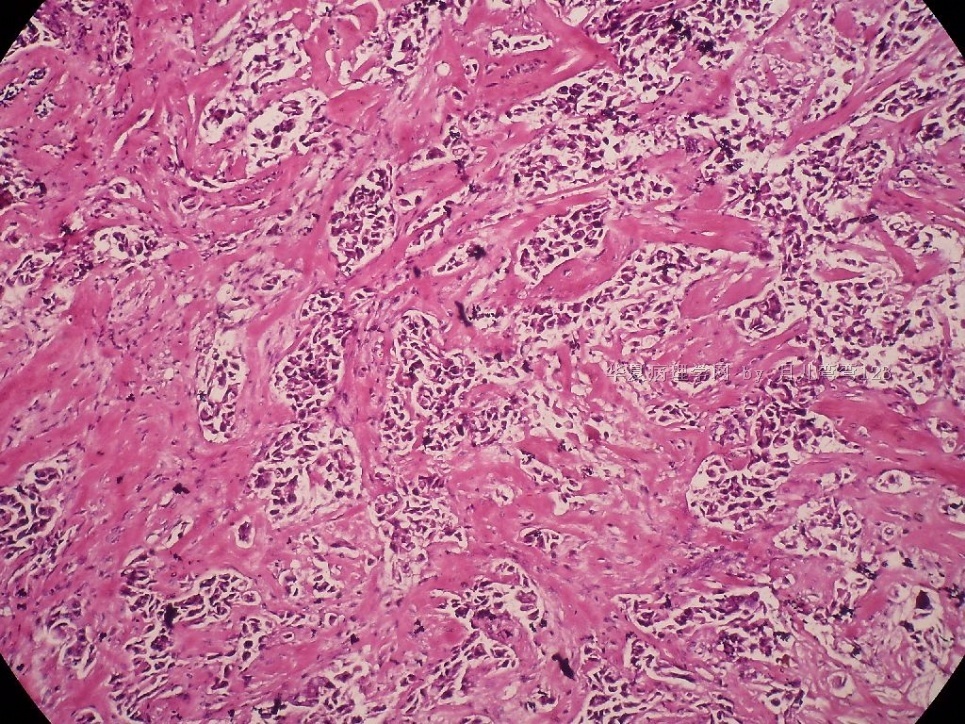

姓    名: ××× 性别:  女 年龄:  45

标本名称:  左侧近乳晕处肿物

简要病史:  患者描述有疼痛

肉眼检查:  肿物一个2.5*2*1厘米,切面灰白质地硬。

• 浸润性导管癌?图4

图4

上皮样细胞,大部分粘附成团成巢,明显浸润。大部分细胞大,核级别高,少数图中见松散的小细胞。未见原位癌。

大细胞考虑浸润性导管癌(3级),小细胞要排除小叶癌。如果有条件请做免疫组化。

Most likely it is INVASIVE DUCTAL CARCINOMA.

DO ER/PR/HER2 STAINS

应该是浸润性导管癌,标本可能有部分自溶现象。